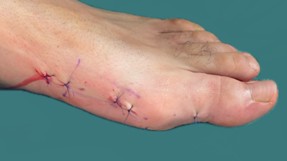

Os procedimentos cirúrgicos são adequados à deformidade que o doente apresenta (exame objetivo e radiografias). As mais utilizadas são as osteotomias distal do 1ºmetatarso em chevron e osteotomia de Akin da falange proximal do hallux. Em casos muito severos, em que haja uma grande artrose da articulação metatarsofalângica do hallux, a artrodese (fusão desta articulação) pode estar indicada para controlo sintomático e de realinhamento do pé.

Os procedimentos cirúrgicos podem ser realizados por técnicas abertas ou técnica percutânea, por exemplo, através de pequenos orifícios, por onde são introduzidos os instrumentos para corrigir a deformidade.

No caso de tratamento cirúrgico, como é o pós operatório?

- Pode caminhar com o auxílio de canadianas e com o sapato pós cirúrgico, após dia 1.

- Primeiro penso pós-operatório na avaliação da 1ª consulta.

- Retira pontos na avaliação da 2ª consulta.

- Inicia retirada de sapato às 4 semanas e colocação de sapato confortável.